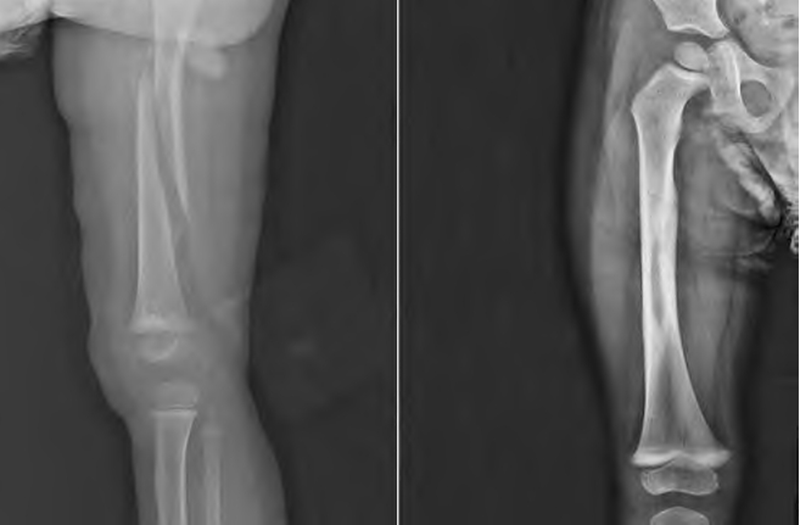

皮牵引治疗儿童股骨干骨折

3.牵引后石膏、支具外固定:髋人字石膏固定适用于6月龄~3岁闭合性股骨干骨折患儿,但不适用于断端缩短大于2cm、复合伤或开放性骨折患儿。对于短缩大于2cm的低龄儿童股骨干骨折,不能即刻采用石膏外固定,此时多采用皮牵引或骨牵引后石膏或支具外固定。在牵引方式选择上,临床多首选皮牵引,便于骨折初始疼痛管理。但需注意,由于皮肤牵引及石膏固定治疗一般时间长,护理不当,容易出现皮肤过敏、压疮、皮疹,严重者出现足下垂、皮肤脱落等并发症。为避免此类并发症的发生,患者出院时应向家属交代出院后护理重点即防止出现皮肤并发症,密切观察双下肢皮肤情况,若出现过敏、起水泡等要及时处理,定时变换体位检查皮肤情况,防止压疮形成。